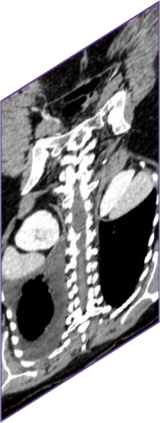

Due to the constraints of the imaging device and high cost in operation time, computer tomography (CT) scans are usually acquired with low intra-slice resolution. Improving the intra-slice resolution is beneficial to the disease diagnosis for both human experts and computer-aided systems. To this end, this paper builds a novel medical slice synthesis to increase the between-slice resolution. Considering that the ground-truth intermediate medical slices are always absent in clinical practice, we introduce the incremental cross-view mutual distillation strategy to accomplish this task in the self-supervised learning manner. Specifically, we model this problem from three different views: slice-wise interpolation from axial view and pixel-wise interpolation from coronal and sagittal views. Under this circumstance, the models learned from different views can distill valuable knowledge to guide the learning processes of each other. We can repeat this process to make the models synthesize intermediate slice data with increasing inter-slice resolution. To demonstrate the effectiveness of the proposed approach, we conduct comprehensive experiments on a large-scale CT dataset. Quantitative and qualitative comparison results show that our method outperforms state-of-the-art algorithms by clear margins.